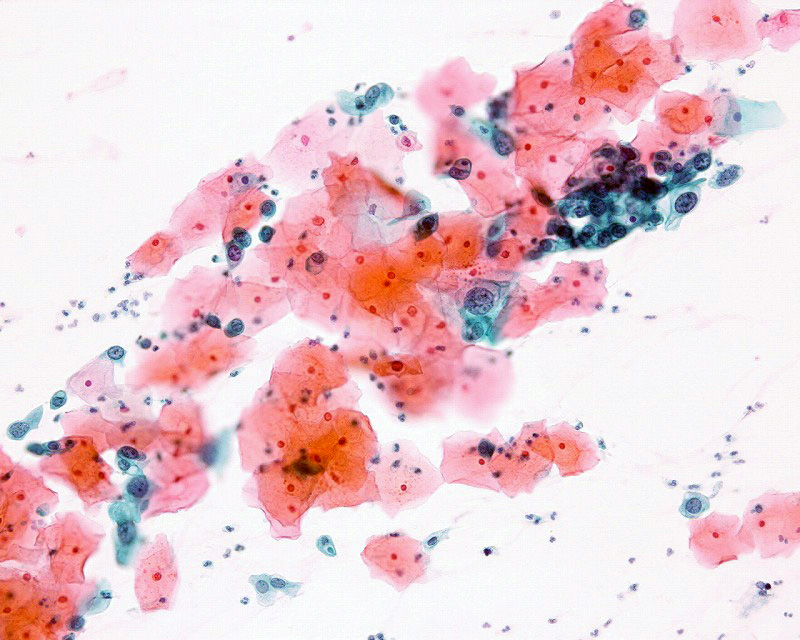

材料:子宮頸部擦過 年齢:40歳   臨床所見:不正出血